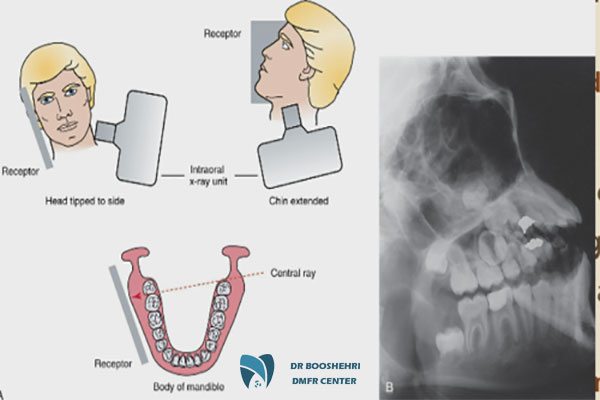

Extraoral imaging offers significant benefits that are especially critical for special patients. One of the most important advantages is its high precision in identifying jaw issues and anomalies. Extraoral imaging can non-invasively capture high-resolution images of various oral structures, teeth, and jaw joints, which are essential for more accurate treatments.

This type of imaging is particularly useful for special patients, especially those who need detailed assessments due to specific conditions such as systemic diseases, jaw anomalies, or bone problems. Ultimately, the great advantage of extraoral imaging is that it can be used for planning complex surgeries or long-term treatments.